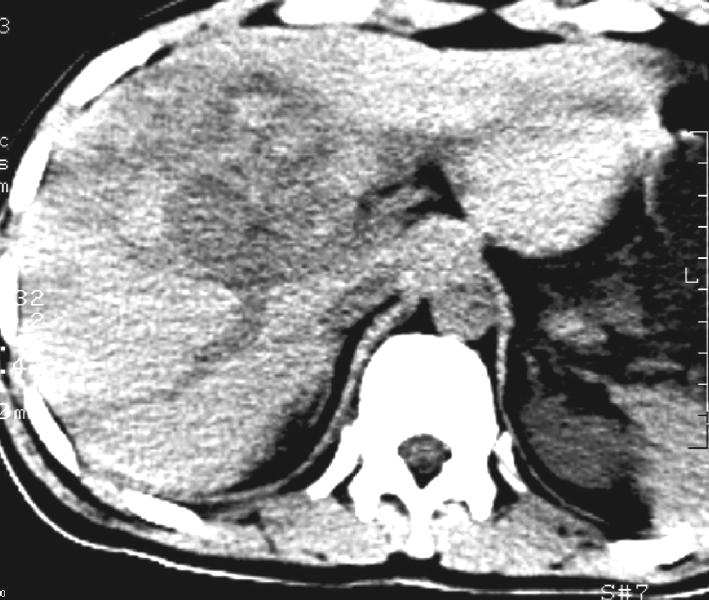

标题: CT11005:男,40岁,左股骨骨折术后10余天,现在感右上腹痛。

b超:右前叶不均质占位。是肿瘤出血还是肝挫伤?以前没有症状啊,10多天后腹部才疼痛。

肝挫裂伤伴血肿形成.

右侧胸腔积液,又有外伤史,肝脏混杂密谋影,考虑肝挫伤可能性大.

右侧胸腔积液,又有外伤史,肝脏混杂密度影,考虑肝钝性挫伤可能性大。

结合病史,考虑为:肝挫裂伤。建议:追踪复查。

结合病史,考虑为:肝挫裂伤。建议复查。